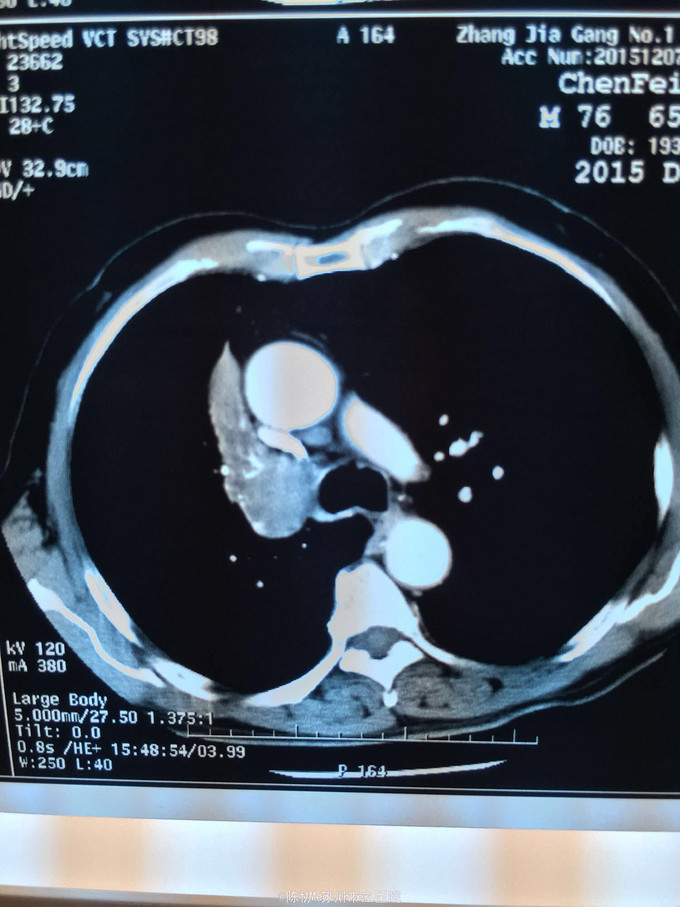

主诉:体检发现右上肺不张半月 77岁男,半月前体检发现右上肺不张,无不适。无消瘦,无咳血,无干咳。去年4月右上肺炎,抗生素治愈,当时CT未见肺肿块。入院支气管镜发现右上支气管开口组织增厚闭塞,开口近侧有隆起约3x3平方毫米,取活检5块病理示中度非典型增生。CT提示在右侧主支气管外侧有30x30平方毫米块影,压迫右上支气管开口处。三大常规和生化检查正常,肿瘤指标正常,TAP正常。

右侧中央型肺癌 重做支气管镜,精于定位找到病症组织,获得病理诊断来指导治疗。 胸外科医生不建议手术,理由是肿瘤位置靠近主支气管和气管,袖状切除不一定看干净。 请问正确的诊断,和比较合理的治疗方法是什么?求助大家思考评论